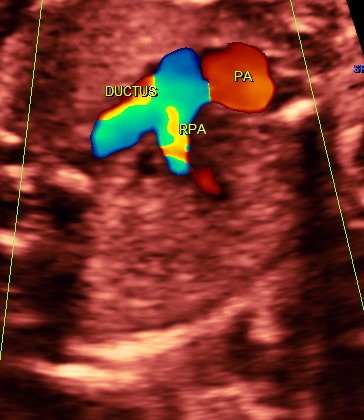

RV outflow tract with dilated Pulmonary trunk dividing into the Rt Pulm artery and the ductus seen. Aorta is not made out. ; SVC is seen